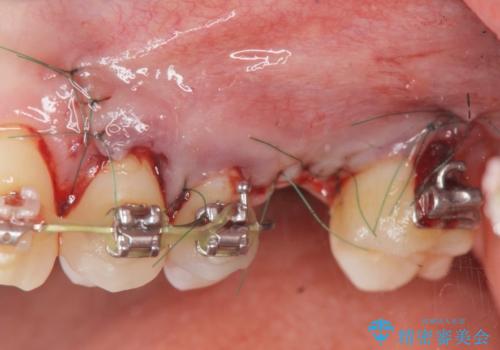

- 他院での矯正治療中、欠損した左上奥歯のインプラント治療を希望され来院されました。

最終的な歯の位置を矯正の担当医と綿密に相談しながら、インプラントの埋入部位を決定し治療にあたりました。

骨量が少なかったことから、上顎洞内へのソケットリフト方をインプラント埋入と同時に施行しています。

矯正治療により最終的な歯のポジションは動いてしまうことからインプラント埋入部位を綿密に検討する必要があります。